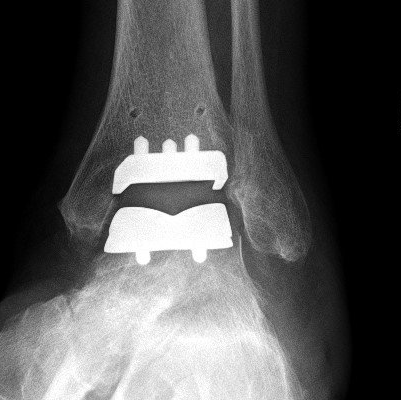

Ankle Replacement (Ankle Arthroplasty)

Replacing the ankle surfaces with metal and plastic has been available for many years but the results have been nowhere near as good as hip and knee replacement.

Ankle replacement technology continues to develop as our understanding of why these implants fail also develops. Better design, materials and patient-specific instruments are making the current generation of implants (2015 and beyond) more reliable (see images below).

Only small numbers are performed in Australia (729 in 2024). For comparison, 30000 hip and 33000 knee replacements are performed each year.

Ankle movement after ankle replacement is not normal. Some restriction and stiffness is common. Significant pain relief occurs in 70% of people.

All joint replacements eventually wear out and "fail". If an ankle replacement needs removing (revision), some are converted to fusion. Re-operation rate (20% at 10 years - for impingement, cysts, etc) and revision rate (14% at 10 years) are still higher than those of hip and knee replacement. Newer implants seem to be doing better.

Ankle replacement is offered to selected people with ankle arthritis. These include low-demand people, those older than 65 years, people with previously fused hindfoot joints, and those with rheumatoid or sero-negative inflammatory arthritis.